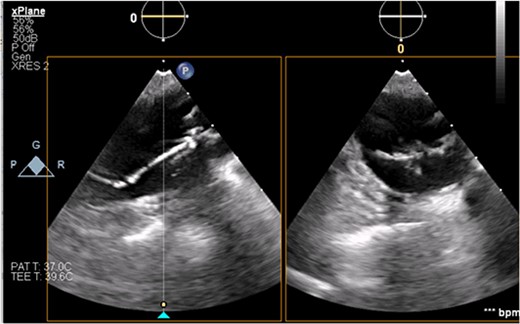

The patient’s milrinone dose was unable to be increased due to his risk for VT and his marginal blood pressures. A 50 cc 8 French left axillary IABP with proximal and distal markers was placed under fluoroscopy and transesophageal echo (TEE) guidance to prevent worsening of end-organ dysfunction and cardiogenic shock. About 3.5 weeks later, the patient received a heart transplant. His 20 gauge right radial arterial catheter was used for monitoring. There were no identifiable changes in the arterial line and the pressure waveforms. The patient was ambulatory in the intensive care unit (ICU) and showed no signs of decreased perfusion. After induction of general anesthesia, TEE showed the IABP in his aortic arch and ascending aorta with its tip placed proximally in the descending aorta (Figs 1 and 2).

Transesophageal image of the ascending and descending aorta with mispositioned IABP present.